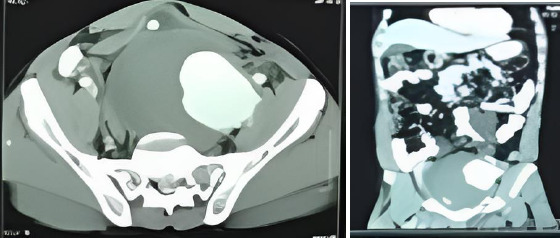

Isolated internal iliac artery aneurysm (IIIAA) is a rare condition, with limited information available about its symptoms and surgical treatment outcomes, particularly in Ghana. This case report presents the 4-year surgical treatment outcomes of three patients (aged 42, 58, and 22 years) with IIIAA, each exhibiting different clinical presentations. All patients experienced pelvic pain and difficulty walking but had uneventful post-operative recoveries. They made significant progress with physiotherapy and were able to mobilise with a Zimmer frame before discharge. Currently, all three patients are mobilising unaided, and post-operative Computed Tomography (CT) scans show no complications. This report highlights the importance of early diagnosis to minimise complications and improve the prognosis for IIIAA, which often presents asymptomatically and can manifest with a wide range of clinical findings. The study underscores the effectiveness of open surgical repair in achieving positive outcomes for IIIAA patients in Ghana.